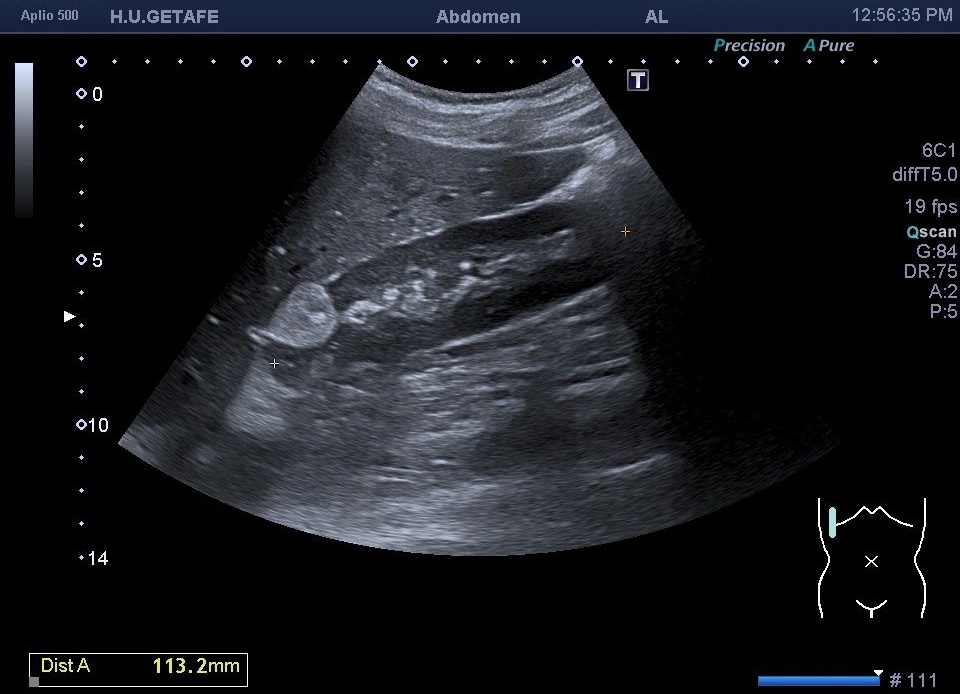

Tiene tres partes la palabra AngioMioLipoma. Hace referencia a vascularizacion, músculo y grasa.

Esa es la composición del tumor benigno del riñón por excelencia.

Ecograficamente son:

1. hiperecogénicos

2. Isoecogénicos con la grasa

3. Homogéneo

4. Corticales

5. Sus bordes son bien definidos

6. Pueden ser lesiones exofíticas

Deben demostrarse siempre en axial y sagital y usar Doppler color y Modo Angio.

El diagnóstico diferencial es el carcinoma, si el tumor visualizado tuviera calcificaciones se sospecharía el tumor maligno como primera posibilidad.

Las complicaciones del AML puede ser la hemorragia.

También conocido como Hamartoma Renal

No suelen dar clínica y en la mayoría de las ocasiones su hallazgo es incidental. De tamaño variable.